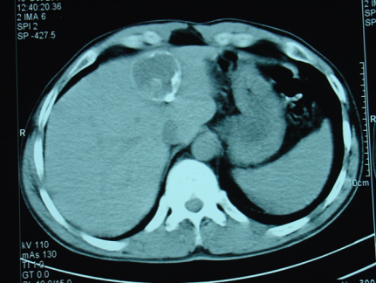

Abses diaqnozunu dəqiqləşdirmək üçün klinik əlmətlərlə yanaşı görüntüləmə və laborator müayinələr aparılmalıdır. Yerli və ümumi sepsis əlamətləri ilə yanaşı USM və ya tomoqrafiyada qaraciyərdə abses boşluğun görünməsi diaqnozu dəqiqləşdirir. Absesdə qaztörədən bakteriyalar olduqda və ya bağırsağa açılarsa içərisində qaz görünür (25%).

Diaqnostik əlamətləri:

• Ağrı, hepatomeqaliya, hərarət, septik əlamətləri

• Laborator septik əlamətlər

• Görüntüləmədə destruktiv ocaq

• Sistlərdən fərqli olaraq abseslərin sərhədi kəskin olmur, möhtəviyyatının sıxlığı yüksək, hətta nekrotik toxumalar olarsa, heterogen görünür.